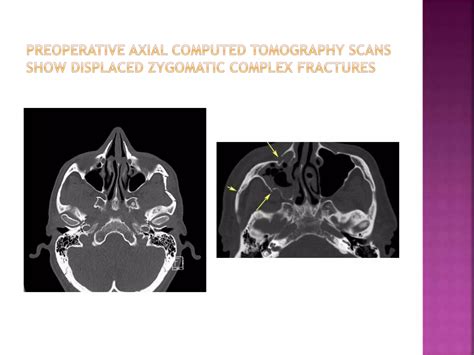

Computed Tomography (CT) scans, specifically axial and coronal views, remain the gold standard for diagnosing these fractures. CT imaging allows the surgeon to visualize the exact degree of displacement, the involvement of the orbital floor, and any potential herniation of orbital contents into the maxillary sinus.